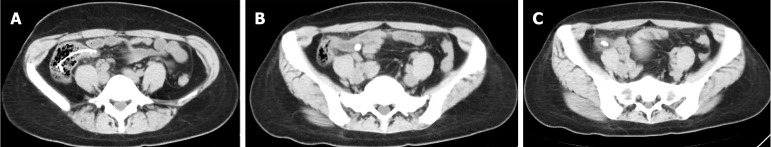

Case summary: We report the case of a 43-year-old female patient presenting with intermittent right lower abdominal pain for one day. The patient had undergone ERAT six months previously. Examination revealed stent impaction in the appendix, leading to exacerbated inflammation. Subsequently, a solo single-incision laparoscopic appendectomy (SSLA) was performed. The ERAT-related complications increased surgical difficulty and prolonged the operation time. Post-SSLA, the patient was hospitalized for one day and showed favorable recovery upon follow-up.